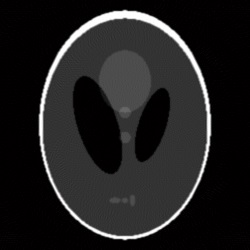

The corresponding sinogram is a matrix with 359 lines and 270 columns. For this set of parameters, the result obtained by the MATLAB implementation of the filtered back-projection algorithm is shown in Fig. 2.

Given the problems we have pointed out regarding the first randomized algorithm, we have focused on the results obtained by the second randomized algorithm. For the parameters that we have fixed above, the results obtained by running the second randomized algorithm with 125000 iterations are given in Fig. 4 and Fig. 5 (Fig. 4 (a) is Fig. 2, and Fig. 5 (a) is Fig. 3). In both cases, the correction is significant, and the result of correction is very close in terms of reconstruction quality to the result obtained by running each of the two analytical algorithms alone with full view of 360 projection angles. That is, the result shown in Fig. 4 (b) is comparable to the result shown in Fig. 6, and the result shown in Fig. 5 (b) is comparable to the result shown in Fig. 7, which means a reduction in the number of views of (in Figs. 6 and 7 the reconstruction is more homogeneous, but with more visible artifacts). From the experiments we have conducted, we have remarked that the number of views can be reduced up to about and the results are still comparable to the results obtained by the analytical algorithms with full view, provided an appropriate number of iterations is chosen.